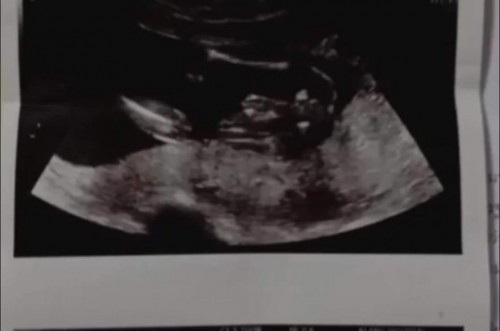

23week อยากทราบเพศ

สอบถามหน่อยค่ะ แบบนี้ผู้หญิงหรือผู้ชายคะ หมอบอกน่าจะผู้ชายค่ะ แม่อยากได้ผู้ชายย😅

กลีบๆผู้หญิงนะคะ ของลูกสาวเราแบบนี้เลย